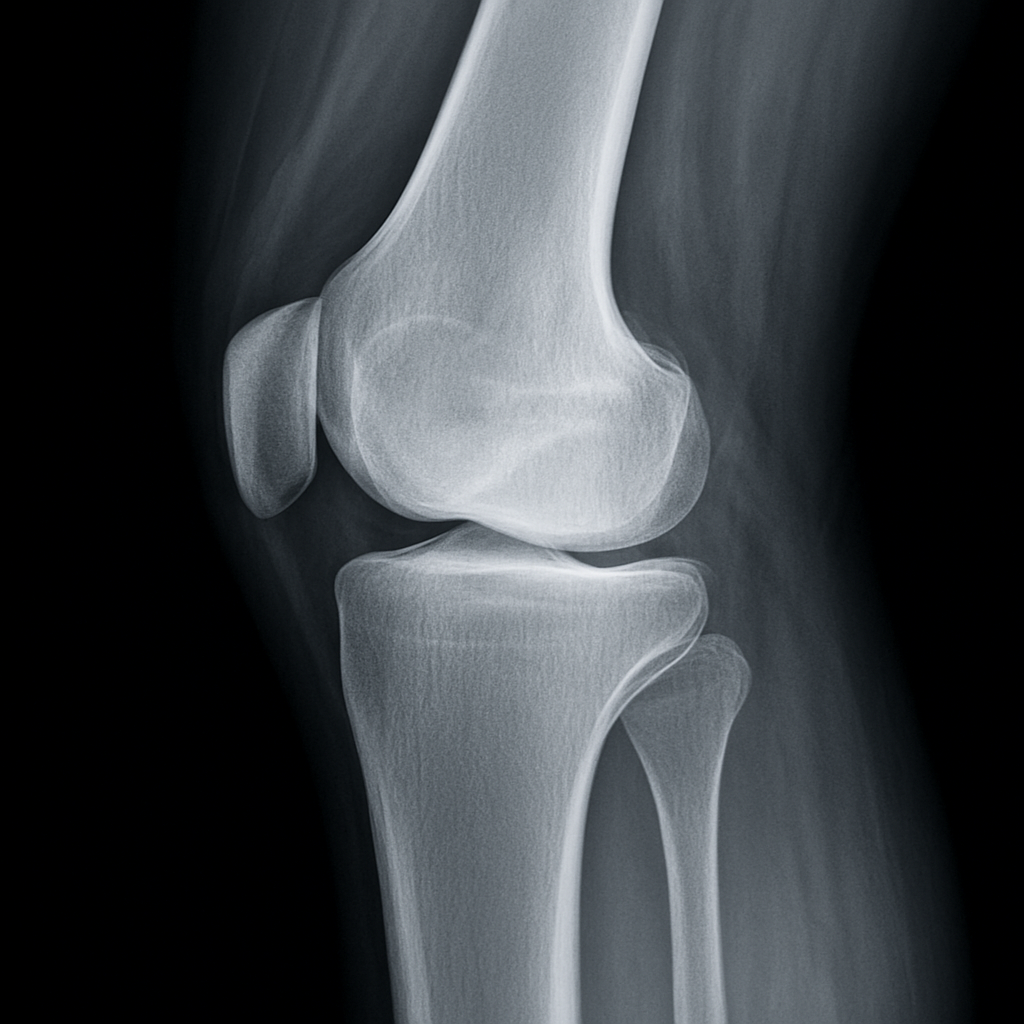

- レントゲンでは異常がないことが多い

- レントゲンで関節の隙間が狭くみえる

■ レントゲンやMRIで異常がなくても痛む理由

鵞足炎は 関節ではなく筋肉の付け根の炎症 のため、

画像検査ではほとんど映りません。